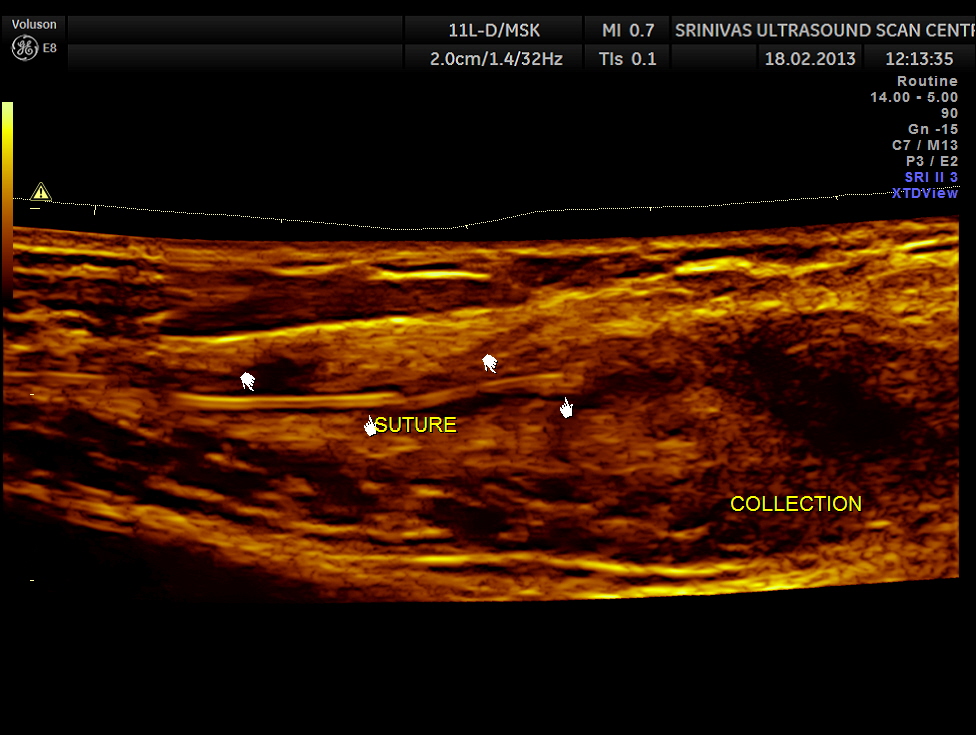

Her routine abdomino pelvic ultrasound scan was normal. The following pictures are acquired with a high resolution 11Mhz transducer.

This revealed unabsorbed suture and irregular collection